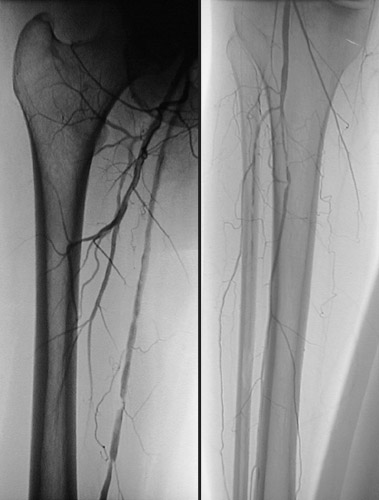

| This patient had poorly controlled type 1 diabetes mellitus for many years and developed claudication in the right lower extremity. An angiogram was performed and revealed multiple areas of atherosclerotic narrowing involving branches of the femoral artery. The upper leg with femur is in the left panel and the lower leg with tibia and fibula in the right panel. |